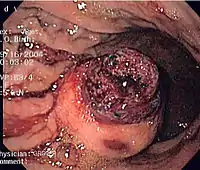

CT scanning is often undertaken (see the radiology section).

The definitive diagnosis is made with a biopsy, which can be obtained endoscopically, percutaneously with CT or ultrasound guidance or at the time of surgery. A biopsy sample will be investigated under the microscope by a pathologist physician. The pathologist examines the histopathology to identify the characteristics of GISTs (spindle cells in 70-80%, epitheloid aspect in 20-30%). Smaller tumors can usually be confined to the muscularis propria layer of the intestinal wall. Large ones grow, mainly outward, from the bowel wall until the point where they outstrip their blood supply and necrose (die) on the inside, forming a cavity that may eventually come to communicate with the bowel lumen.

When GIST is suspected—as opposed to other causes for similar tumors—the pathologist can use immunohistochemistry (specific antibodies that stain the molecule CD117 [also known as c-KIT] —see below). 95% of all GISTs are CD117-positive (other possible markers include CD34, DOG-1, desmin, and vimentin). Other cells that show CD117 positivity are mast cells.

If the CD117 stain is negative and suspicion remains that the tumor is a GIST, the newer antibody DOG-1 (Discovered On GIST-1) can be used. Also, sequencing of KIT and PDGFRA can be used to prove the diagnosis.